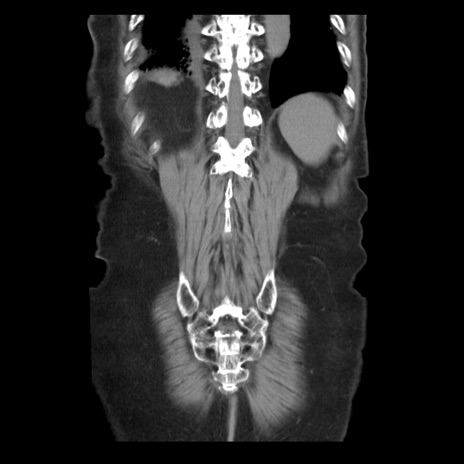

症例21(冠状断像)

【症例】70歳代男性

【主訴】腹痛

【現病歴】肝硬変・肝細胞癌にてかかりつけの方。約9時間前に食後より腹痛出現。症状が徐々に増悪し、嘔吐出現したため来院。

【既往歴】肝硬変、肝細胞癌(RFA、TACE後)

【身体所見】意識清明、表情苦悶様、BT 36℃、BP 129/78mmHg、P 88bpm、SpO2 97%(RA)、右上腹部から心窩部にかけて圧痛あり、反跳痛なし、筋性防御あり。

【データ】WBC 5800、CRP 0.16